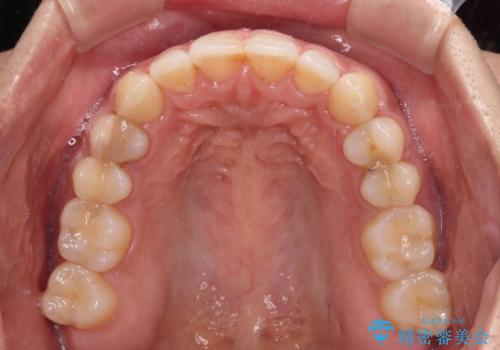

沖縄から飛行機で通院 インビザラインによる矯正治療

- 3年8ヶ月

通院途中に、仕事の都合で東京に来る機会が激減してしまったため、なかなか治療が進まず、当初終了予定であった時期が2年近くずれ込んでしまいました。